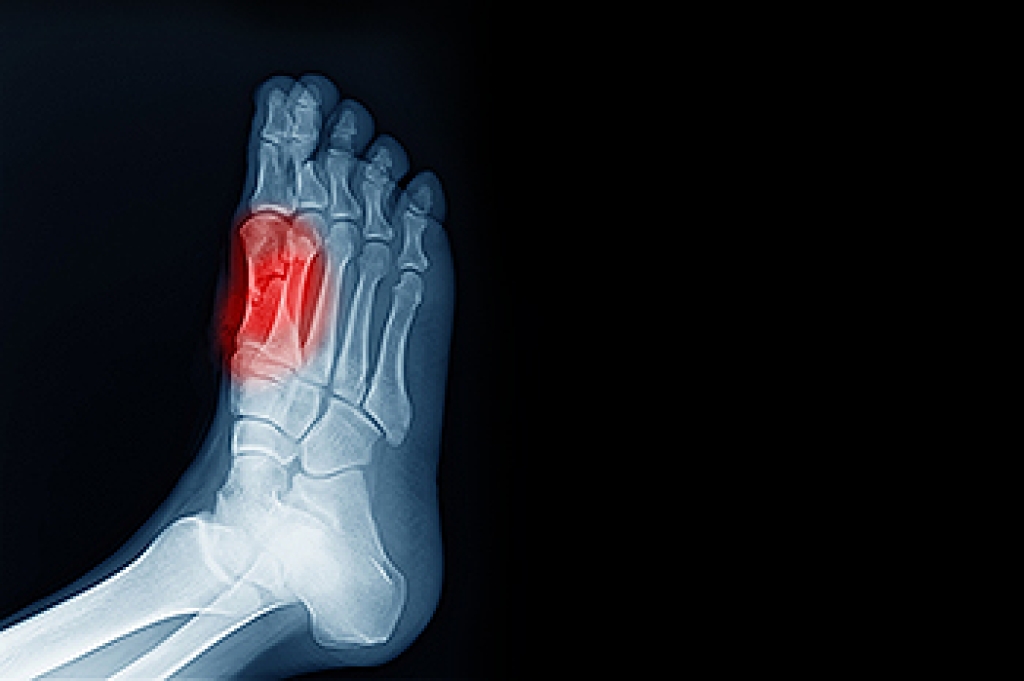

In many cases the cause of toe pain is obvious, but in others, a podiatrist may want to use more advanced methods to determine the problem. These can range from simple visual inspections and sensation tests to X-rays and MRI scans. Prior medical history, family medical history, and any recent physical traumatic events will all be taken into consideration for a proper diagnosis.

Treatments for toe pain and injuries vary and may include shoe inserts, padding, taping, medicines, injections, and in some cases, surgery. If you believe that you have broken a toe, please see a podiatrist as soon as possible.